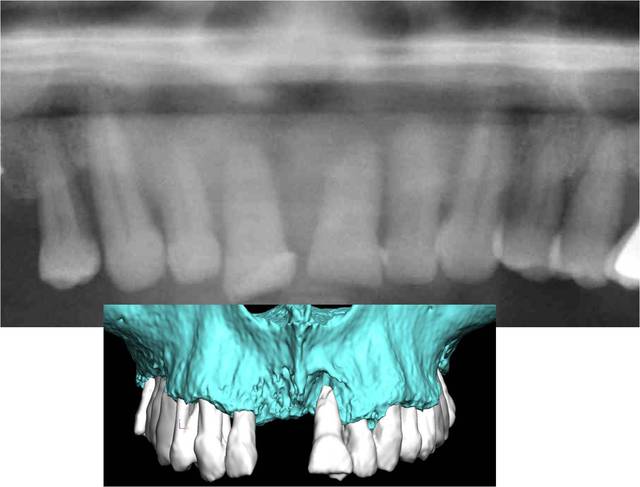

Simple question, pourquoi conserver les dents postérieures (28-38, je pense) qui sont en phase finale de paro ?

L'implant 27 devrait aussi être remplacé, enfin, selon ce qu'on voit sur les images montrées.

Il y avait 9 implants avant la chir 1 va mal et tous vous focalisé, amusant mais classique

Ce n'est pas en rapport avec le sujet mais voila mon raisonement

28 ET 38 sont restées 5 ans car je les pensais utiles

28 n'est pas en rapport avec le problème de l'implant 27

Dans 3 mois 28 & 38 vont disparaitre, et je tenterais en même temps de sauver 27

En cas d'échec probable dans l'implant disparaitra et lors de la prothèse définitive j’intégrerais 26 ou pas